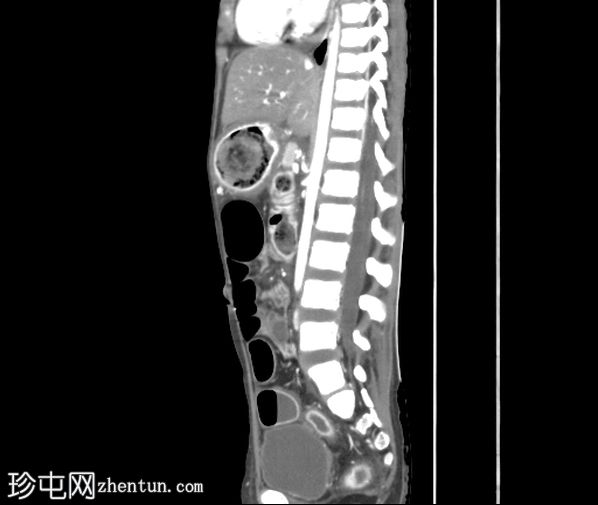

矢状位增强扫描(门静脉期)

胃腔内可见巨大肿块,内含斑驳状软组织、气体和高密度灶,延伸至幽门、十二指肠和近端空肠(长发公主综合征)。十二指肠轻度扩张。

胃壁强化减弱及胃壁积气区域。

当胃石穿过幽门延伸至十二指肠和空肠时,这种情况被称为长发公主综合征。患者会出现腹痛、呕吐、早饱,有时还会出现体重减轻。CT 扫描具有很高的敏感性,可以显示管腔内肿块,其内部呈斑驳状气体分布,且在管腔造影剂的照射下边界清晰。